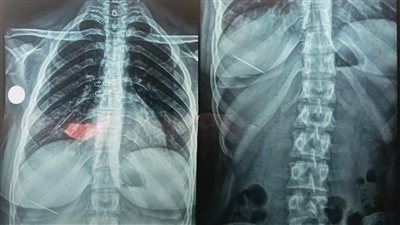

بلعت دبوس الطرحة.. إنقاذ فتاة من اختناق حاد في مستشفيات جامعة المنوفية

الأحد 03/08/2025 10:47 م